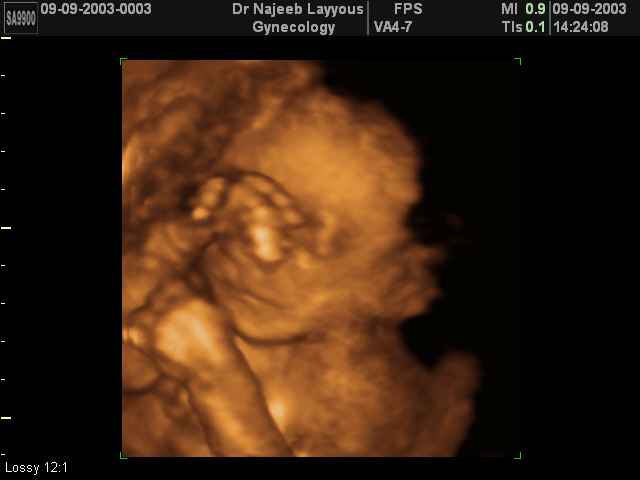

- تصرفات الجنين داخل الرحم

- صور لوجه الجنين في داخل الرحم

- صور لتصرفات الجنين داخل الرحم

صور لتصرفات الجنين داخل الرحم بجهاز الالتراساوند ثلاثي الأبعاد | الدكتور نجيب ليوس